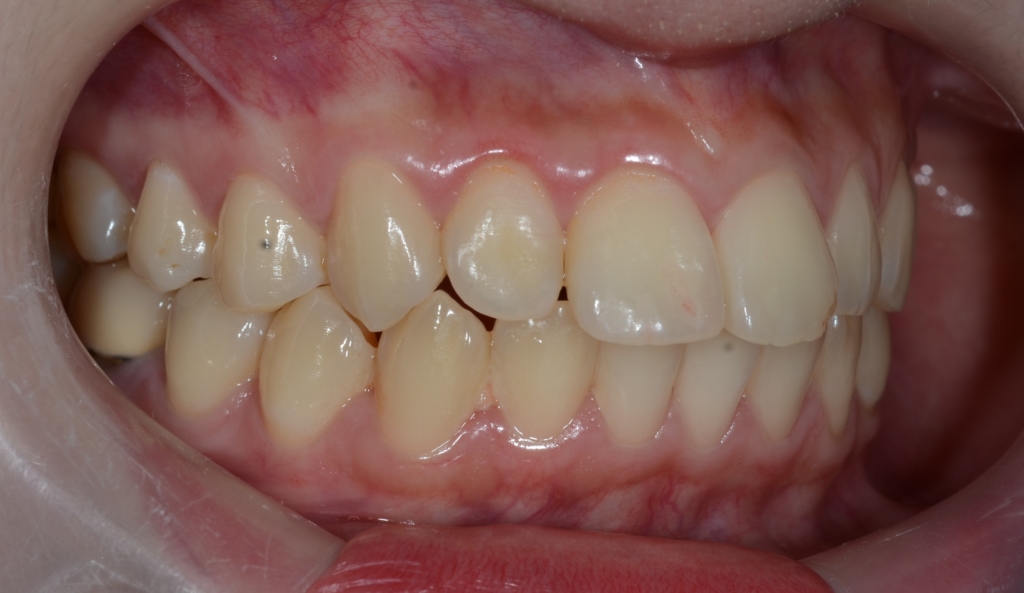

ついでに、歯並びの比較です

上段が矯正治療前、下段が矯正治療後